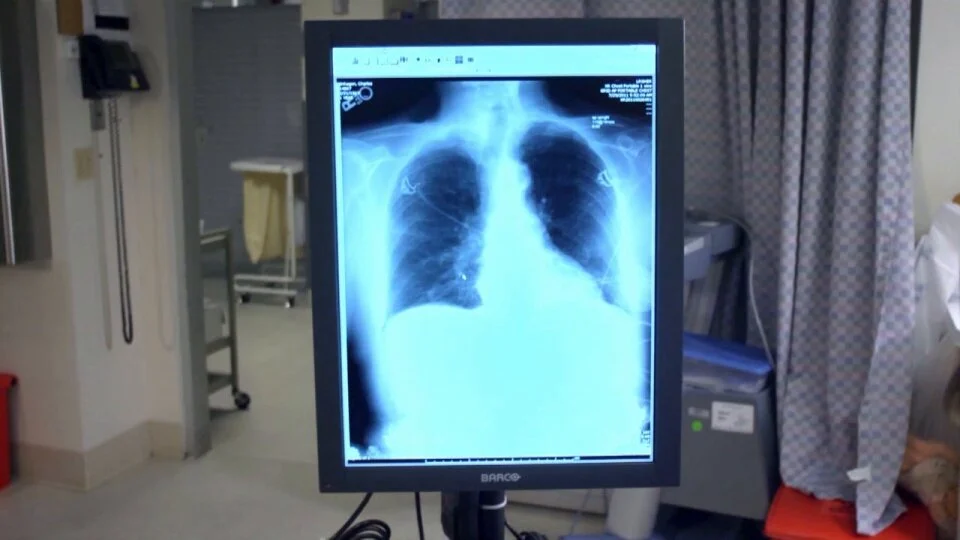

Portfolio

Here are some of the prominent clients and brands Craig has worked with: